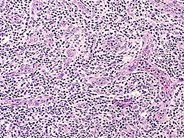

Angioimmunoblastic T Cell Lymphoma - 12.

CD20 stain in pattern I, low power (1995).